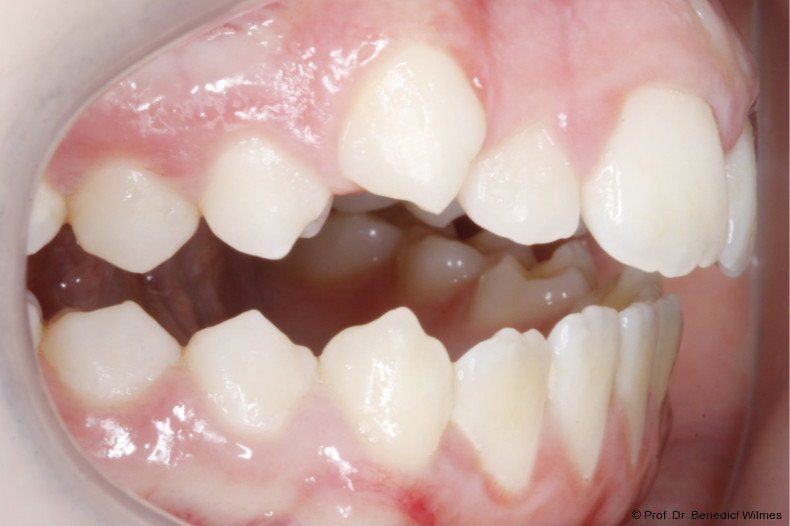

Eine 13-jährige Patientin stellte sich mit beidseitigem Kreuzbiss, einem anterioren offenen Biss und einer Angle Klasse II vor. Das viszerale Schluckmuster wurde mittels logopädischer Maßnahmen umgestellt, der offene Biss persistierte jedoch (Abb. 3a–l).